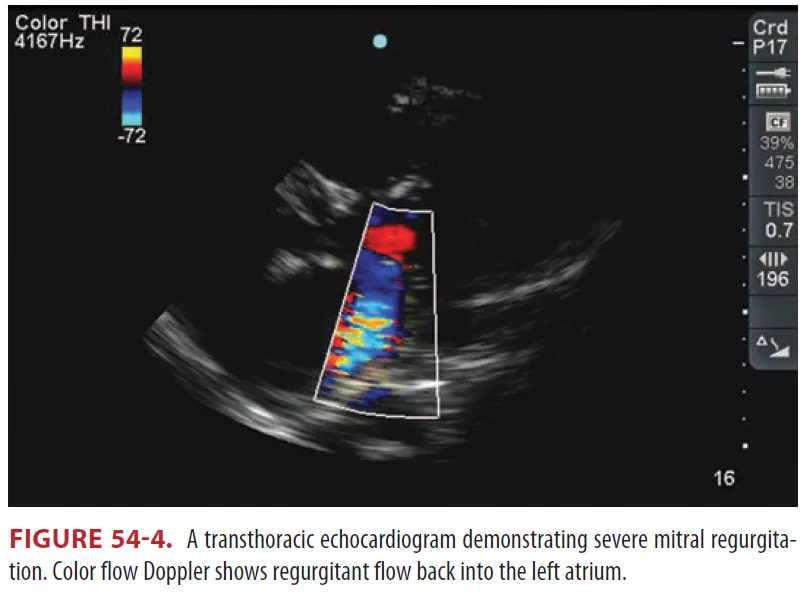

(3) Transthoracic echocardiography → Transthoracic echocardiography or cardiac MRI